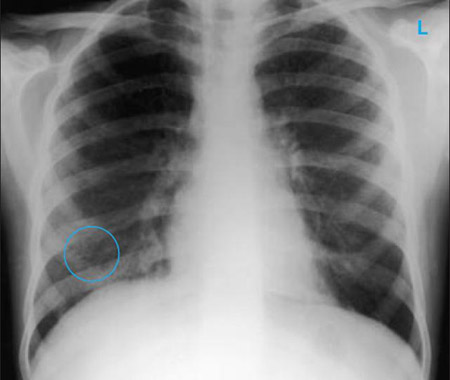

Uma radiografia torácica deve ser obtida no início da avaliação da tosse crônica.[38] Embora não seja diagnóstica das causas mais comuns, os achados podem facilmente desviar a avaliação para causas de maior gravidade como doenças pulmonares estruturais. Eles incluem câncer pulmonar, fibrose pulmonar, tuberculose, bronquiectasia, pneumonia, aspiração e sarcoidose.[Figure caption and citation for the preceding image starts]: Radiografia torácica mostrando hiperinsuflação em paciente com DPOC. A hiperinsuflação é causada pelo componente de enfisema na DPOC, em vez da bronquite crônica subjacente aos sintomas da tosseDo acervo pessoal do Dr. M. A. Sharifabadand, SUNY na Stony Brook School of Medicine, Departamento de Medicina Pulmonar e Intensiva, Mineola, Nova York, e Dr. J. P. Parsons, The Ohio State University Medical Center, Columbus; usado com permissão [Citation ends].

[Figure caption and citation for the preceding image starts]: Radiografia torácica mostrando múltiplos nódulos distintos nos dois pulmões (um deles marcado com um círculo) em um paciente com tuberculose miliarE. Dick, Student BMJ. 2001;9:10-12 [Citation ends].